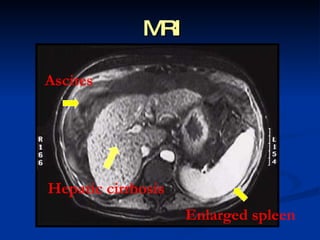

Imaging  Ultrasound   ,  CT and MRI are  routinely used in the evaluation of cirrhosis, where it may show a small and nodular liver in advanced cirrhosis along with increased echogenicity with irregular appearing areas. Ultrasound may also screen for hepatocellular carcinoma, portal hypertension and Budd-Chiari syndrome (by assessing flow in the hepatic vein).

MRI A scites Hepatic cirrhosis Enlarged spleen